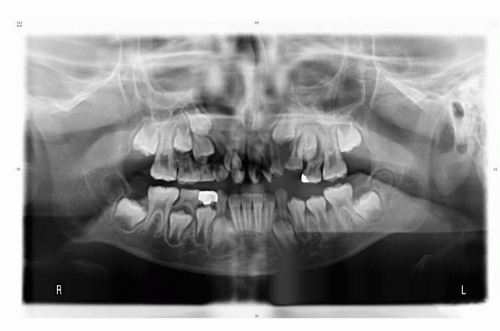

Panoramic x-rays and CT scans are also helpful to evaluate the necessity of bone grafting in the alveolar or cheek region when the patient is older (FIG 7).

In the author’s center, cephalometric and panoramic radiographs and CT scans with 3D reconstruction are routinely recorded every 2 years from ages 5 to 17 years to monitor facial growth.

Bony reconstruction of the alveolar clefts is similar to the timing of alveolar bone grafting in cleft patients, ie, in the mixed dentition period before the eruption of the teeth in the cleft region.